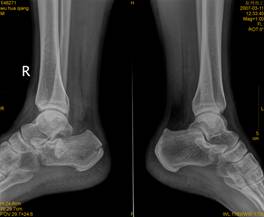

跟骨骨折影像病人有典型的外傷史,患足承重困難和足跟疼痛,局部觸痛、腫脹和皮下淤血斑亦多明顯。在較嚴重的壓縮骨折時,除可見到足後跟的高度變低和足跟橫徑變寬以及外踝下部正常凹陷消失外,距下關節話動亦完全喪失。但跟骨周邊骨折僅有局部腫脹及壓痛,而距下關節活動範圍多屬正常。x線正、側、軸位片可明確跟骨的結節關節角和其橫徑寬度的改變。

影像學表現

(1)跟骨前突骨折。

(2)跟骨結節的垂直骨折。

(3)載距突骨折。

(4)跟骨壓縮性骨折。

(5)跟骨粉碎性骨折。